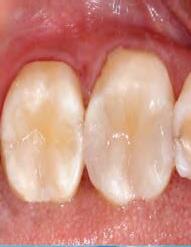

DISTO-OCCLUSAL CLINICAL CASE